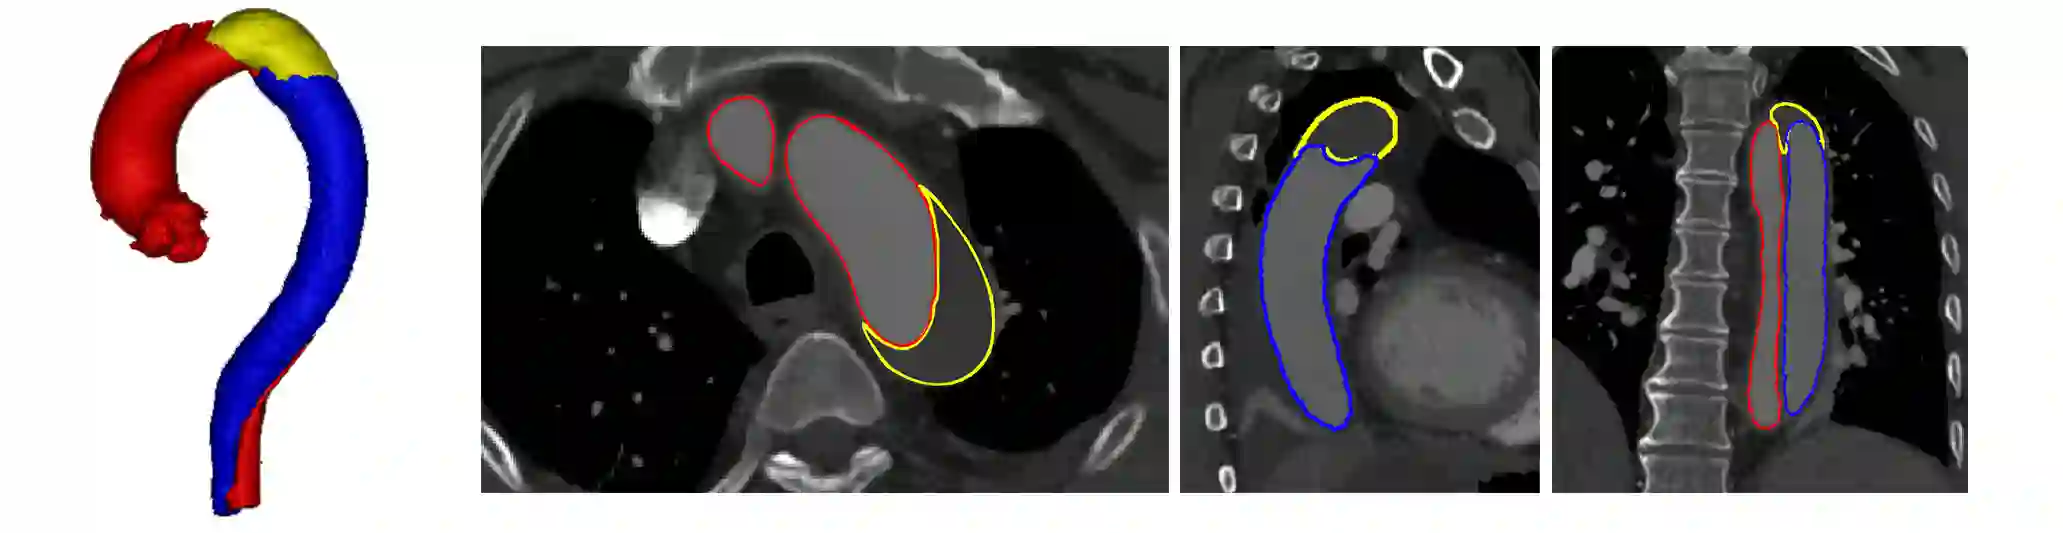

Type-B Aortic Dissection (TBAD) is one of the most serious cardiovascular events characterized by a growing yearly incidence,and the severity of disease prognosis. Currently, computed tomography angiography (CTA) has been widely adopted for the diagnosis and prognosis of TBAD. Accurate segmentation of true lumen (TL), false lumen (FL), and false lumen thrombus (FLT) in CTA are crucial for the precise quantification of anatomical features. However, existing works only focus on only TL and FL without considering FLT. In this paper, we propose ImageTBAD, the first 3D computed tomography angiography (CTA) image dataset of TBAD with annotation of TL, FL, and FLT. The proposed dataset contains 100 TBAD CTA images, which is of decent size compared with existing medical imaging datasets. As FLT can appear almost anywhere along the aorta with irregular shapes, segmentation of FLT presents a wide class of segmentation problems where targets exist in a variety of positions with irregular shapes. We further propose a baseline method for automatic segmentation of TBAD. Results show that the baseline method can achieve comparable results with existing works on aorta and TL segmentation. However, the segmentation accuracy of FLT is only 52%, which leaves large room for improvement and also shows the challenge of our dataset. To facilitate further research on this challenging problem, our dataset and codes are released to the public.